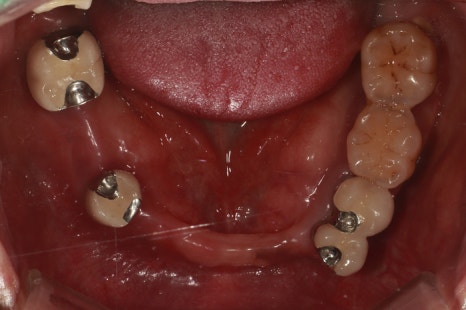

촬영:2024년1월9일

기존 틀니는 이제 아예 들어가지도 않는다며

어디 있는지도 모른다고 하셨습니다.

처음 보철하셨을 때, 치아 모양이 예뻐서

만족스러우셨을 것 같은데

보철 후 구강관리 및 사후관리가 많이 안되어진

모습으로 보입니다.

입안 상태를 보면

상악의 보철 위쪽으로 치조골이 녹아서 치아뿌리가 드러나있고

드러난 치아뿌리로는 치석과 염증이 뒤엉켜

수직적 잇몸흡수가 깊게 일어난 것을 확인할 수 있습니다.